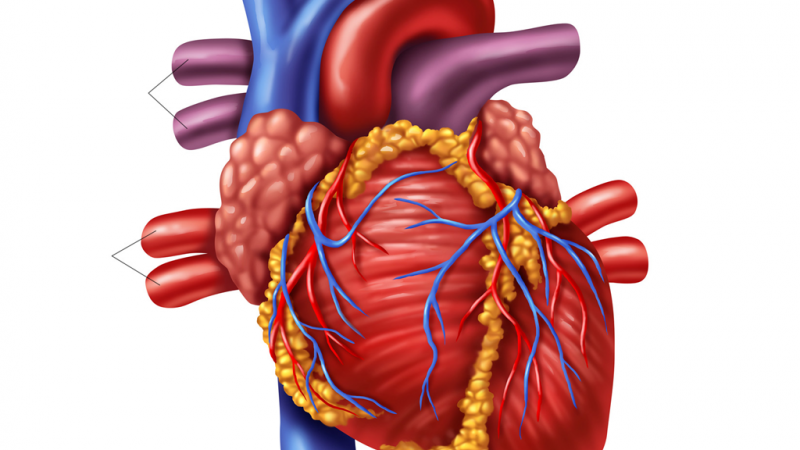

Identify areas of the human heart.